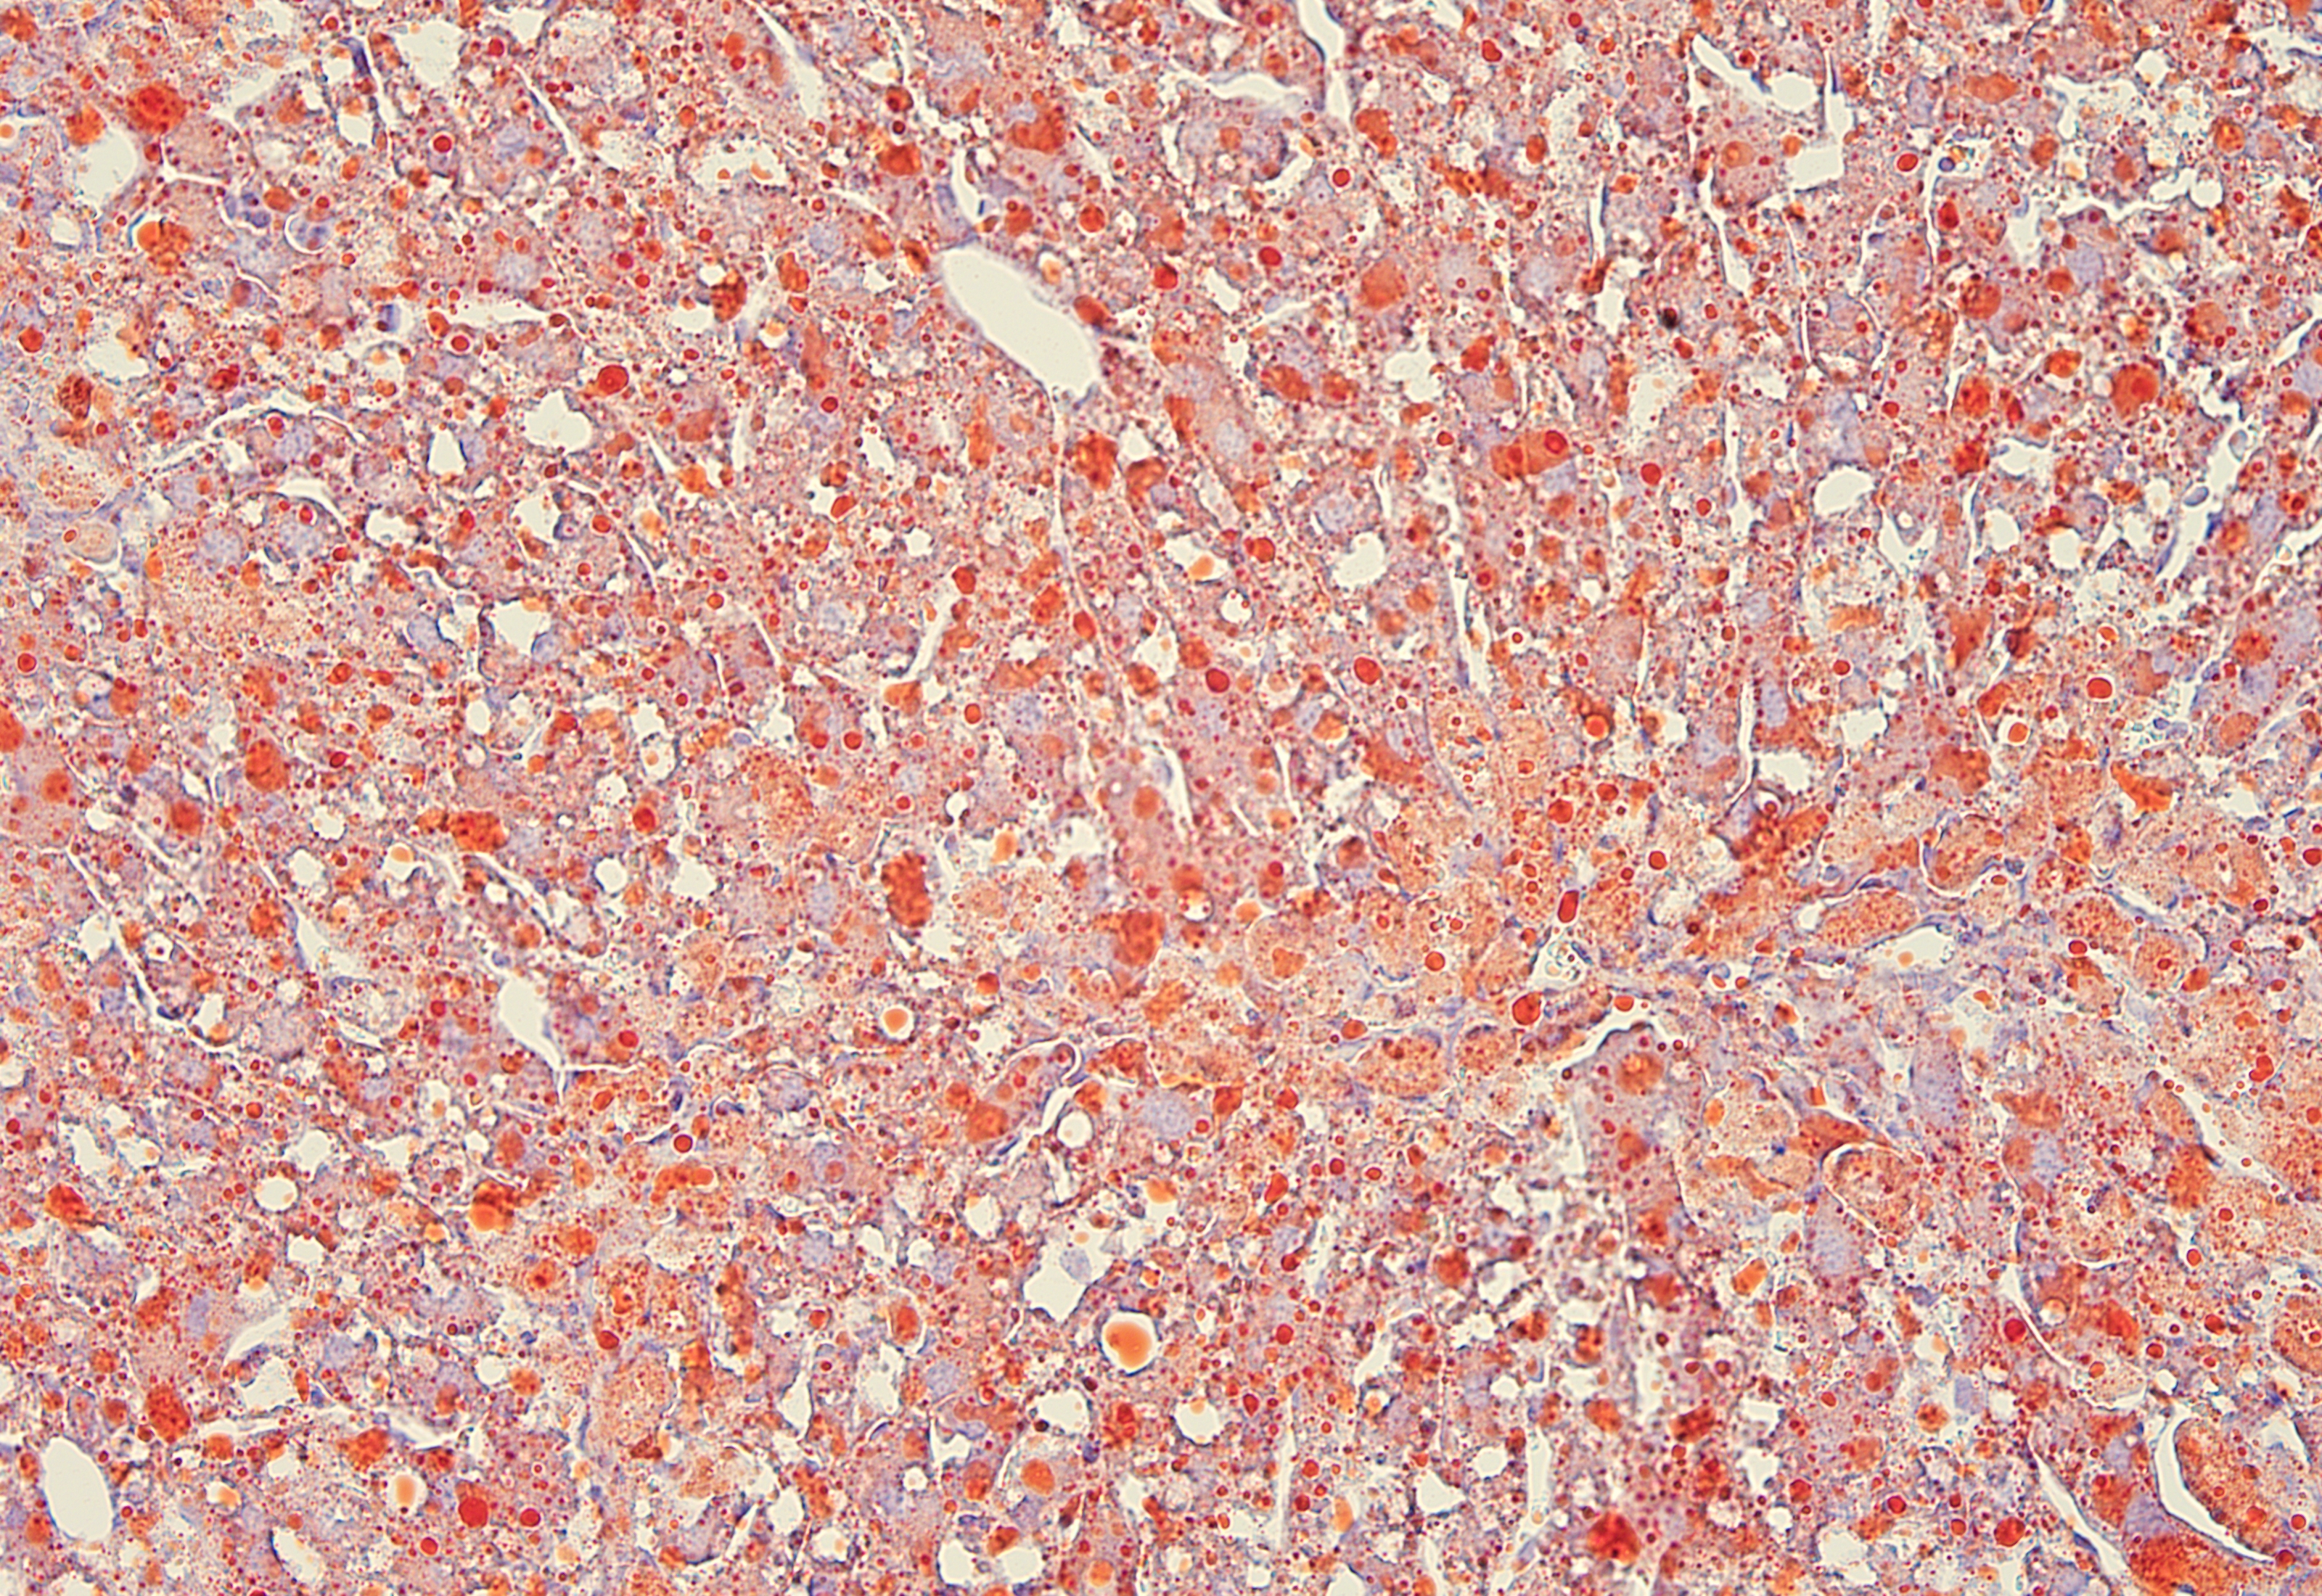

油红O染色

油红O脂肪染色法是指在日常病理诊断和科研工作中为了显示组织内的脂肪常采用油红O进行染色的方法,油红O为脂溶性染料,在脂肪内能高度溶解,可特异性的使组织内甘油三酯等中性脂肪着色。

脂肪肝模型动物的肝脏油红 冰冻切片染色